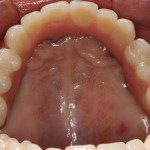

Realizado em: Agosto de 2012Detalhes do tratamento: Implantes instalados imediatamente após extrações de dentes inferiores e prótese fixa sobre implantes (instalada 72 horas após a cirurgia).

Fiz tratamento odontológico com Dr. Alexandre e Dra. Mariza. Foi muito bom, gostei muito e estou muito satisfeita. Com Dr. Alexandre fiz cirurgia e implante. Foi muito bom não sentir dor, foi perfeito. Com Dra. Mariza fiz prótese fixa sobre implante inferior e prótese total “normal” superior. Estou muito satisfeita com o trabalho deles!